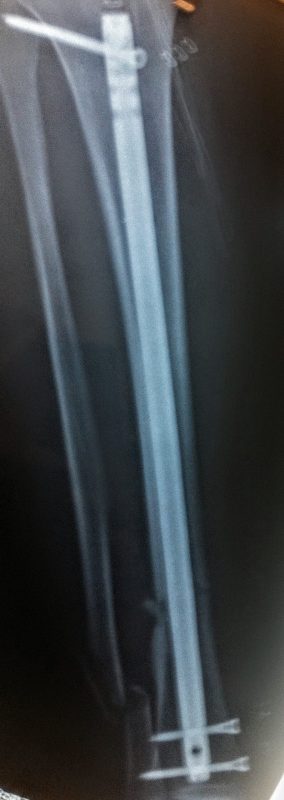

Τα κατάγματα της Διάφυσης των οστών της κνήμης και του Μηριαίου οστού στη σύγχρονη ΟΡΘΡΟΠΑΙΔΙΚΗ αντιμετωπίζονται με ΕΝΔΟΜΥΕΛΙΚΗ ΗΛΩΣΗ.

Δύο τομές 3 εκατοστών και 1 εκατοστού αντιστοίχως για την εισαγωγή και το κλείδωμα του ήλου μέσα στο οστό. Η μέθοδος είναι κλειστή,σχεδόν αναίμακτη,διάρκειας 60 λεπτών,με τη βοήθεια C-ARM (τηλεόρασης).

Στον ασθενή παρέχεται οπτικό υλικό (όλα τα χειρουργικά στάδια) σε CD ή Στικάκι,λόγω της δυνατότητας καταγραφής του χειρουργείου από το C-ARM Ο ασθενής περπατάει άμεσα μετεγχειρητικά στις 5 ώρες μετά την επέμβαση και εξέρχεται από το νοσοκομείο σε 1 -2 ημέρες.